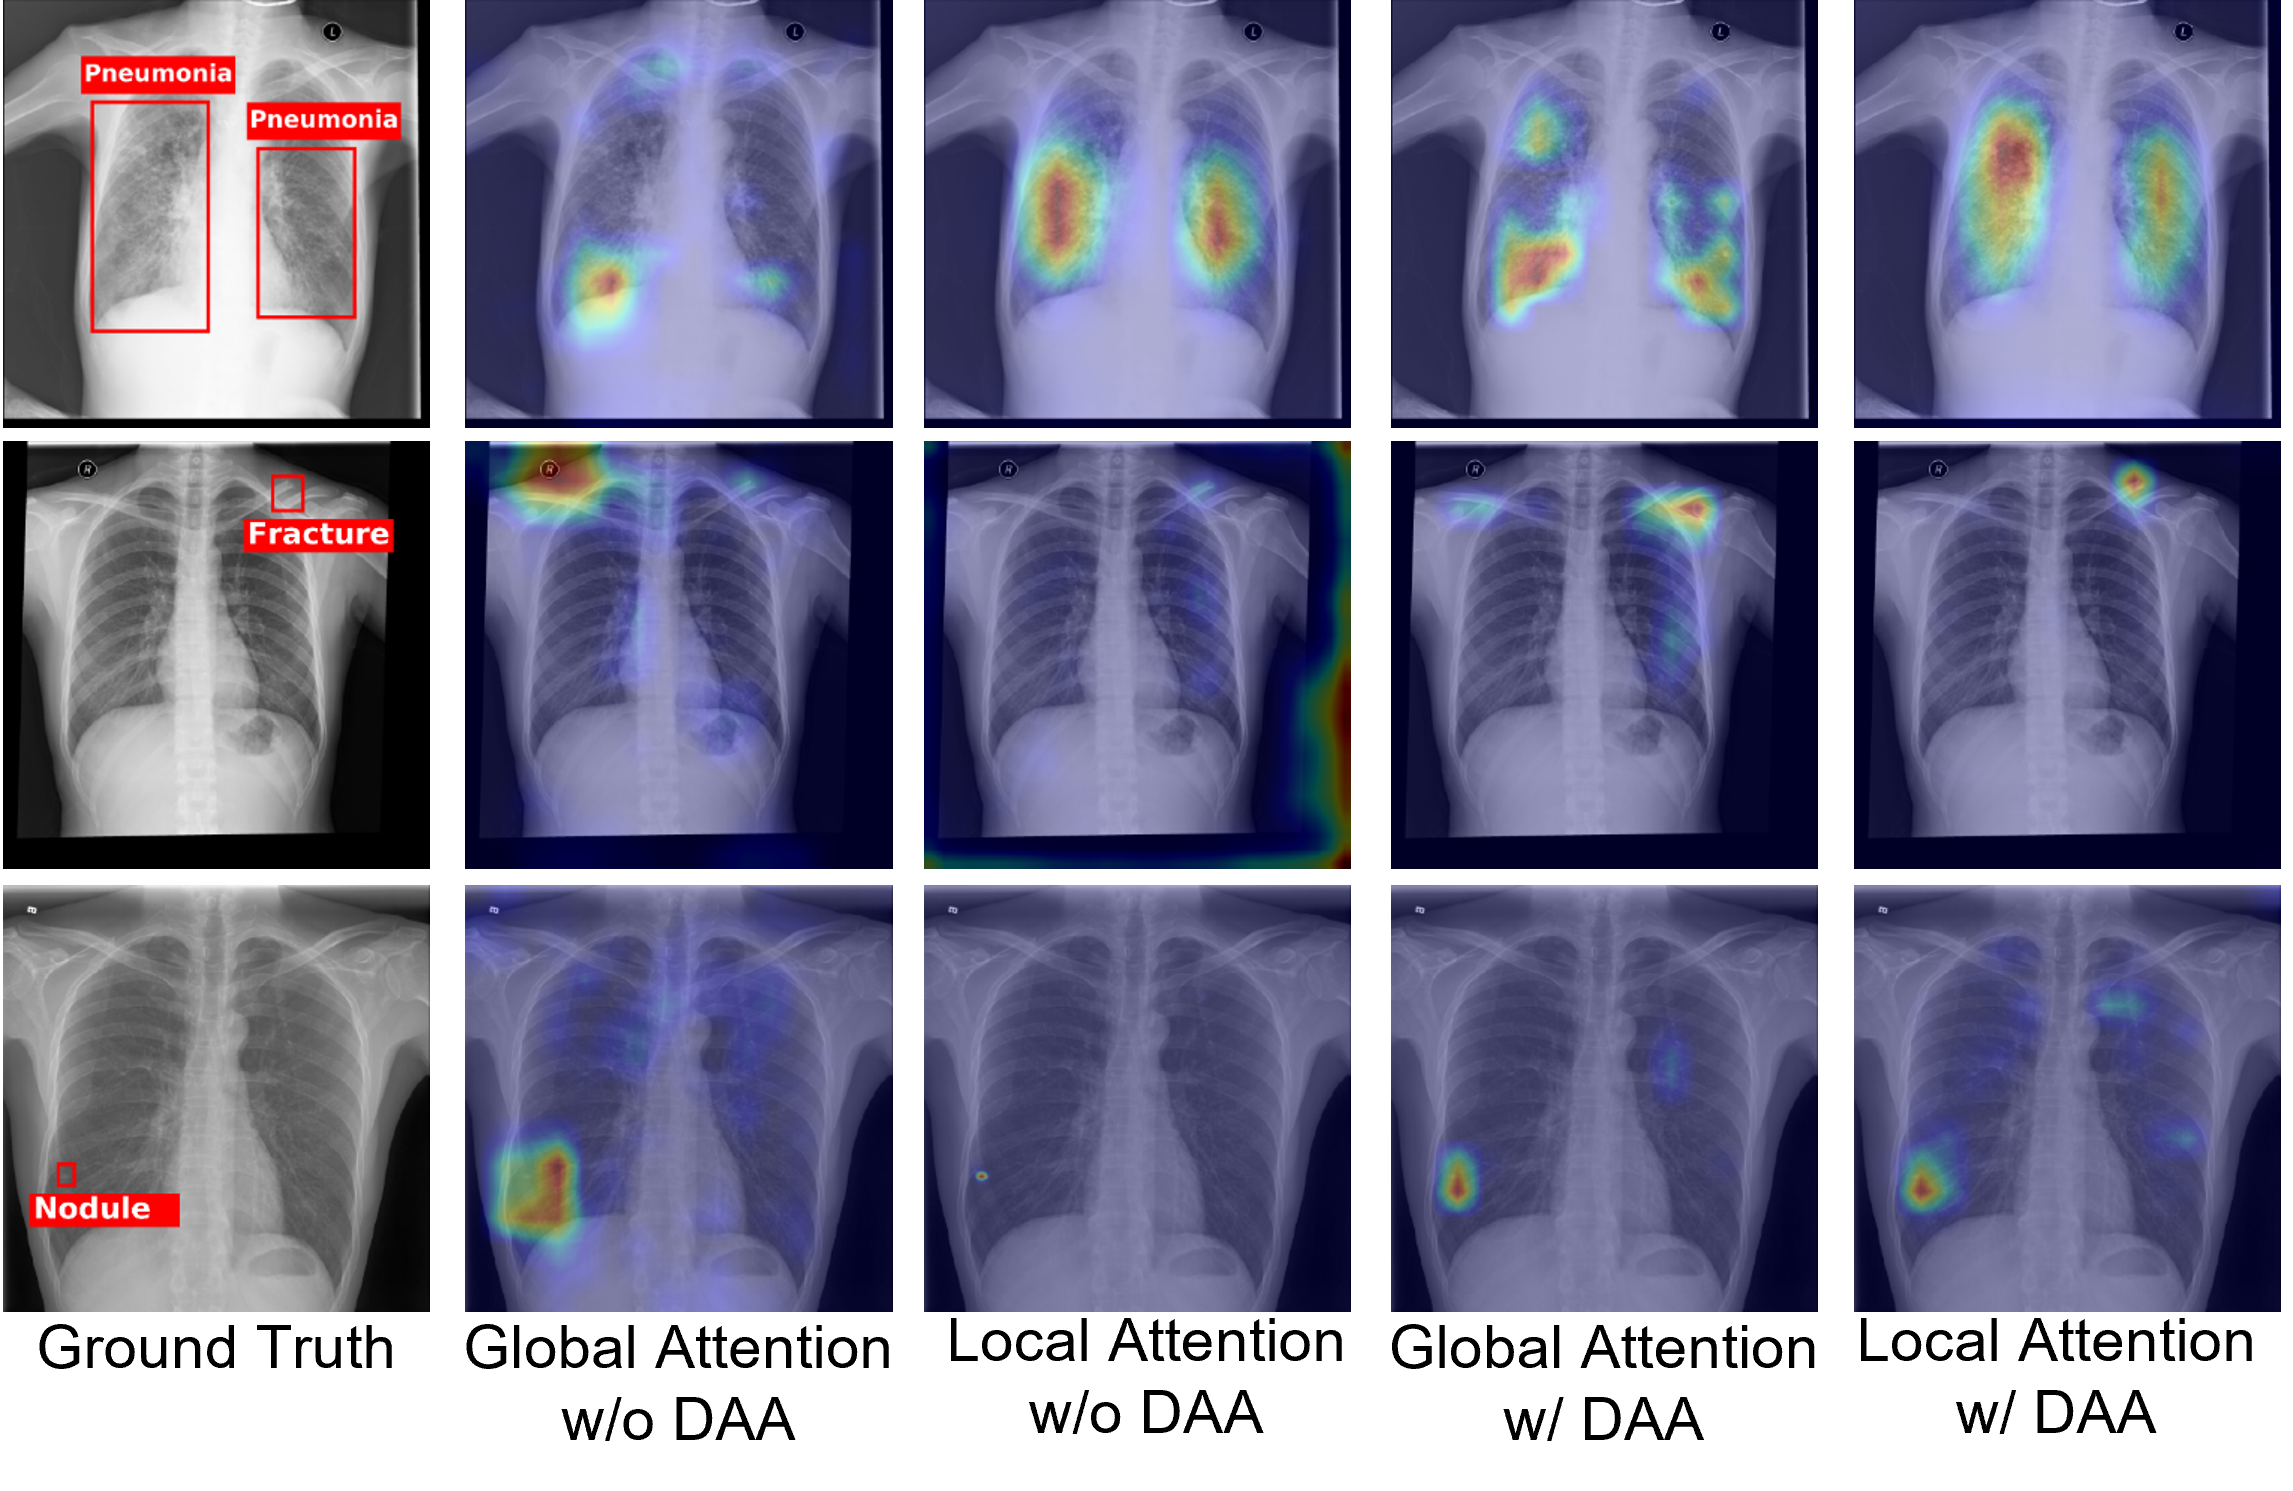

ORFNet

Deep Omni-supervised Learning for Rib Fracture Detection from Chest Radiology Images

Zhizhong Chai, Luyang Luo*, Huangjing Ling, Pheng-Ann Heng, Hao Chen

IEEE Transactions on Medical Imaging (IEEE TMI), 2024

OXnet

OXnet: Deep Omni-supervised Thoracic Disease Detection from Chest X-rays

Luyang Luo, Hao Chen*, Yanning Zhou, Huangjing Lin, Pheng-Ann Heng

International Conference on Medical Image Computing and Computer-Assisted Intervention (MICCAI), 2021